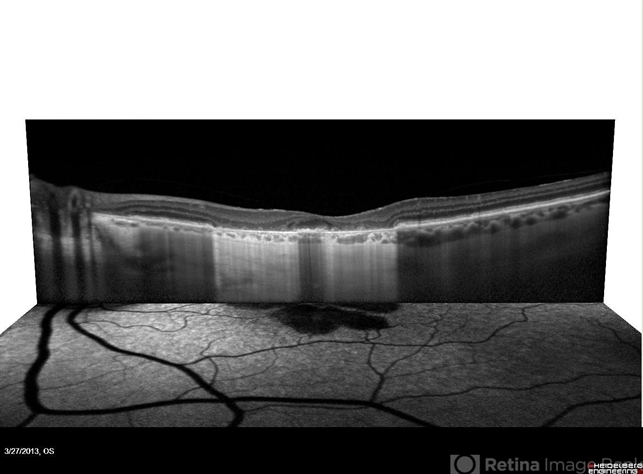

- optical coherence tomography (OCT), fundus autofluorescence (FAF), geographic atrophy, enhanced depth imaging, foveal sparing

Optical coherence tomography system

Heidelberg Spectralis - Description

- This is a combined FAF/SD-OCT in EDI mode of a patient with geographic atrophy and foveal sparing.